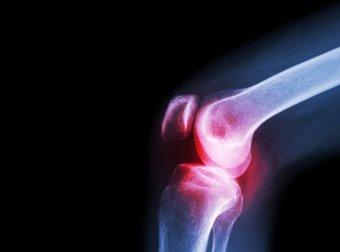

É importante notar que a maioria dos casos acontece devido às bactérias. Podemos destacar os estafilococos e estreptococos. Pode ocorrer em qualquer idade, mas surge com mais frequência em bebês. O quadril e o joelho são os mais afetados..

Os sintomas variam dependendo do tipo de infecção. As infecções bacterianas geralmente afetam uma única articulação. Normalmente, eles ocorrem no joelho ou no quadril. Qualquer movimento dessa articulação é muito doloroso. Os sintomas costumam se manifestar rapidamente. Além disso, eles geralmente são acompanhados por febre e calafrios.

Além disso, o médico pode solicitar um raio X da articulação afetada. Raios X e outros testes de diagnóstico por imagem podem ajudar a avaliar os danos.